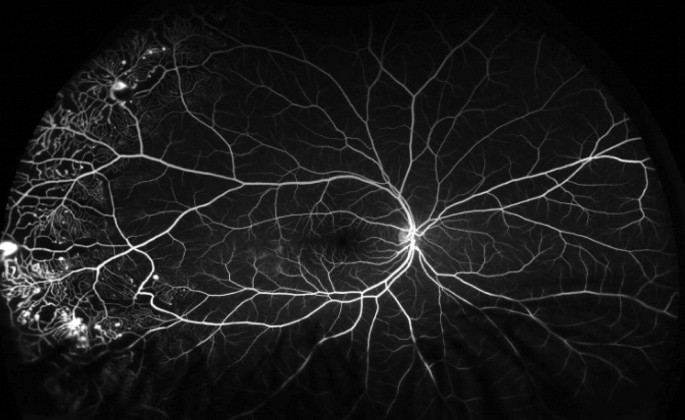

UWF-FA was obtained in 14 (25%) patients and abnormal FA findings were detected in 12 patients (86%). In the patients who received fluorescein angiography, the angiographic phases were evaluated (Table 2). None of the patients had capture of early choroidal filling (0%). Six of the 14 patients (43%) had capture of the arterial phase. All patients (100%) had capture of the venous and recirculation phases. The average visible quadrants ranged from 3.7 to 4 quadrants. An example of a patient who received an UWF-FA with Coats disease in clinic is shown in Fig. 4.

Three patients who received UWF-FA had been previously treated with anti-VEGF or laser photocoagulation for ROP or Coats disease. UWF-FA confirmed adequate treatment and guided the decision to observe. An example is shown in Fig. 5. Three other patients who received UWF-FA were treated with laser ablation for Coats disease based on wide field imaging findings. An example is shown in Fig. 6. One patient with newly diagnosed Coats disease required subsequent anesthesia for performance of laser photocoagulation. No patients required subsequent examination under anesthesia for diagnostic purposes.

Similarly, UWF-FA was particularly useful to confirm lack of activity or guide targeted panretinal photocoagulation in retinal vascular diseases [2, 9,10,11]. Moreover determining if a child who was previously treated requires additional treatment can be challenging. A negative UWF-FA, meaning one without significant ischemia or leakage, can guide the decision to observe with serial examinations and photographs and eliminate the need for an exam under anesthesia as shown in Fig. 4. On the contrary, a UWF-FA with active leakage or neovascularization as in a patient with proliferative diabetic retinopathy or Coats disease may indicate the need for additional panretinal photocoagulation (Fig. 5).